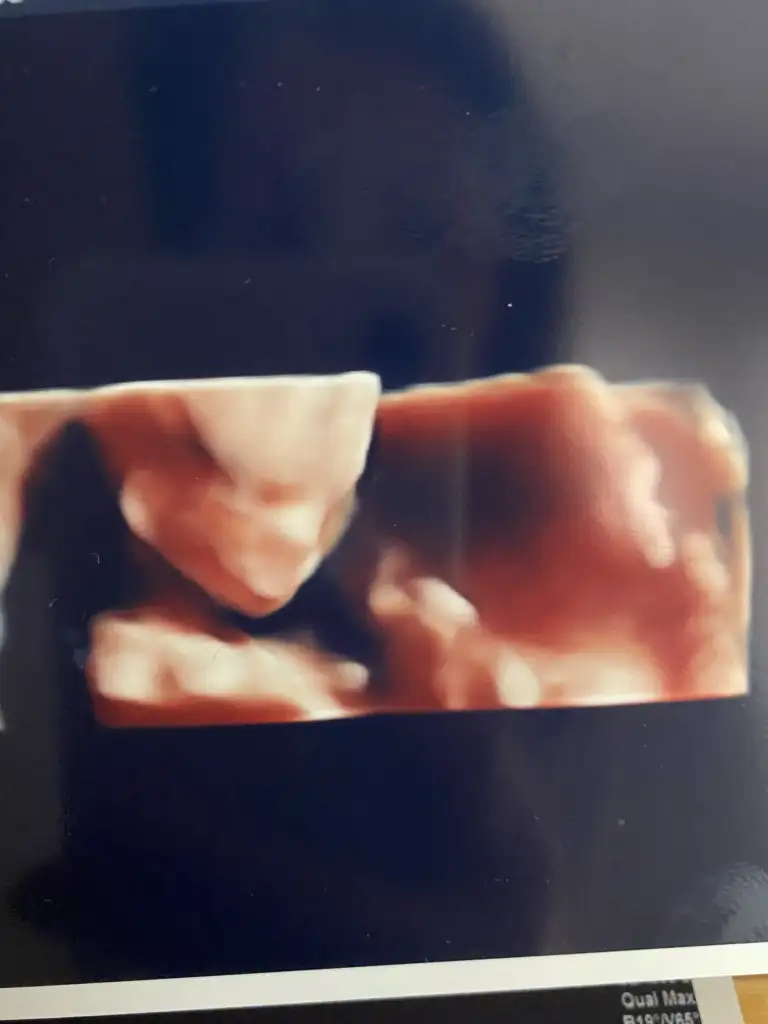

Teyzeleri bu da benim kız 🥰🥰 dün ne pozlar ne el sallamalar zıplamalar ablasıyla gittik ilk defa, o da izlerken mest oldu 😘